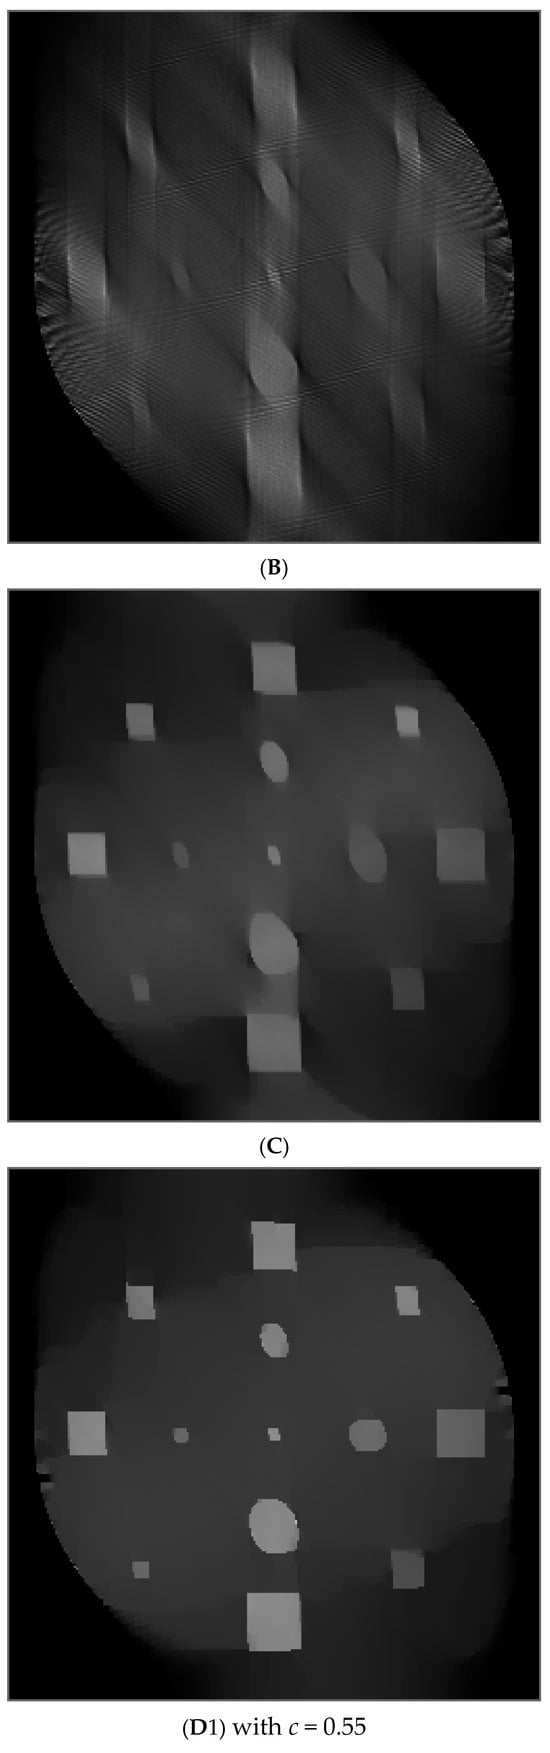

In the computer simulations, the parallel-beam imaging geometry was considered. The scanning angle for the first phantom was 40°, and for the second phantom was 90°. The image size was 256 × 256. For these two phantom studies, three image reconstruction algorithms were compared in Figure 8 and Figure 9, respectively: The well-known MLEM algorithm [34], the MLEM-TV algorithm [33], and the proposed POCS revised L0-norm minimization algorithm.

Figure 8.

Results of the first phantom study. (A) True phantom; (B) MLEM reconstruction; (C) TV reconstruction; (D1, D2) Proposed revised L0 norm reconstruction.

The iteration number was 400 in the POCS algorithm. Within each iteration, there were 10 iterations of the MLEM algorithm for data fidelity enforcement and 10 iterations of the gradient decent algorithm for piecewise-constant enforcement.

The only tuning parameter in the MLEM algorithm is the number of iterations. However, the gradient descent algorithm has two tuning parameters: the number of iterations and the step size. The step size was chosen as 0.0001 in the first phantom reconstruction and was 0.00001 in the second phantom reconstruction.

The MLEM reconstruction has the most limited-angle artifacts, and the shapes of the small objects are not well defined. The TV reconstruction slightly improves the boundaries of the small objects in the image. The most significant improvement is achieved by the proposed POCS L0 minimization algorithm.

Table 2 and Table 3 show the quantitative evaluation results with the structural similarity (SSIM) [39] and the peak signal-to-noise ratio (PSNR) [40] for the two phantom studies, respectively. An SSIM value closer to 1 indicates better image quality. A greater PSNR value indicates better image quality.